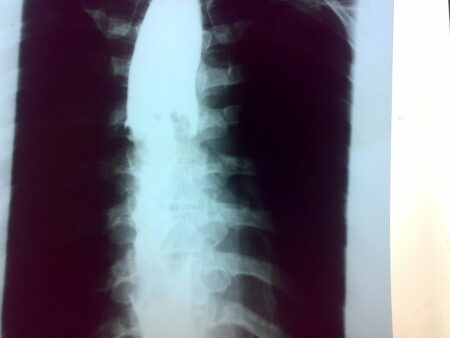

Courtesy of Geoff Livingston (Flickr CC0)

Esophageal cancer is a silent killer. It is on the rise among middle-aged Americans. Its rate doubled among individuals aged 45 to 64, and the prevalence of a precancerous condition called Barrett’s esophagus rose by 50% between 2012 and 2019.

The esophagus carries the liquid and food from the throat to your stomach. According to the study by Dr. Bashar Qumseya, chief of endoscopy and associate professor of medicine at the University of Florida, the exact reason for the uptick of esophageal cancer is the soaring rates of an unhealthy diet, obesity, and gastroesophageal reflux disease (GERD) or chronic heartburn.

Chronic heartburn leads to Barrett’s esophagus, marked by abnormal changes in the cells lining the esophagus.

Esophageal Cancer

Courtesy of Saltanat ebli (Wilimedia CC0)

Doctors typically recommend screening colon cancer patients at 50, but due to the compelling evidence seen in younger people, the screening now starts at 45. The screening may be the same with esophageal patients with other risk factors like smoking and alcohol use.

Qumseya recommends endoscopy screening for colon cancer in individuals with reflux and other risk elements. This disease was dubbed a silent killer because the symptoms are noticeable when cancer has progressed.

The researchers peeked for esophageal cancer in 5 million people in Florida by tapping into the electronic health archives.

Cancer rates plateaued among the oldest group, and the climb in middle-aged adults is not because of assertive screening. Qumseya and his associates planned to discern squamous cell carcinoma and esophageal adenocarcinoma data to determine risk elements and possible rationales.

It is disturbing to cite that cancer, considered an elderly disease, is becoming a lifestyle-dependent ailment impacting the younger generation.